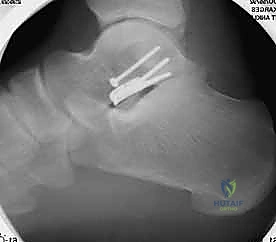

المرحلة الرابعة: التثبيت الداخلي (Internal Fixation)

بمجرد التأكد من أن العظم عاد لشكله الطبيعي تماماً، يتم استبدال الأسلاك المؤقتة بتثبيت دائم. يستخدم الدكتور هطيف أحدث الغرسات الطبية العالمية:

* مسامير التيتانيوم المجوفة (Cannulated Screws): مسامير قوية جداً يتم إدخالها عبر العظم لضغط أجزاء الكسر معاً.

* المسامير بدون رأس (Headless Compression Screws): تُستخدم في المناطق المغطاة بالغضروف، حيث تُدفن بالكامل داخل العظم لكي لا تحتك بالمفصل وتسبب تآكلاً.

* الشرائح المعدنية الدقيقة (Mini-Plates): تُستخدم أحياناً لتدعيم التثبيت في حالات التفتت الشديد (Comminution) حيث لا تكفي المسامير وحدها.

يتم وضع المسامير عادة من اتجاهين (من الأمام للخلف، ومن الخلف للأمام) لإنشاء هيكل ميكانيكي صلب يتحمل الضغوط.

المرحلة الخامسة: التحقق الإشعاعي الفوري والإغلاق

قبل إنهاء العملية، يستخدم الدكتور هطيف جهاز الأشعة السينية المتحرك داخل غرفة العمليات (C-arm Fluoroscopy) لأخذ صور متعددة والتأكد من:

1. المحاذاة المثالية للكسر.

2. عدم وجود أي فجوات أو درجات في السطح المفصلي.

3. الطول والموقع الصحيح للمسامير (للتأكد من أنها لا تخترق المفاصل المجاورة).